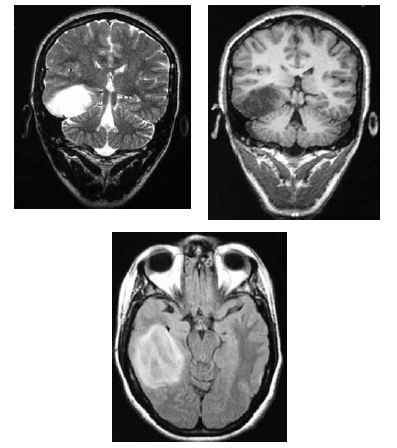

Uma mulher de 36 anos de idade foi encaminhada ao ambulatório de neurologia por dificuldade no controle das crises epilépticas. Ela referiu ter tido uma convulsão febril aos 36 meses e ter passado a ter crises em que ficava “fora do ar” aos 11 anos. Ela recebeu o diagnóstico de epilepsia generalizada do tipo ausência e foi-lhe prescrito fenobarbital. Desde então, já fez uso de primidona, ácido valpróico e diazepam, em monoterapia e associados ao fenobarbital, sem sucesso. No exame, a paciente apresentava um comprometimento da memória recente e aparentava ter um sutil deficit dos campos visuais e Babinski à esquerda. Apesar de trazer um EEG normal, foi solicitada RNM de encéfalo, que é reproduzida abaixo.

Com referência a esse quadro clínico, julgue os itens seguintes.